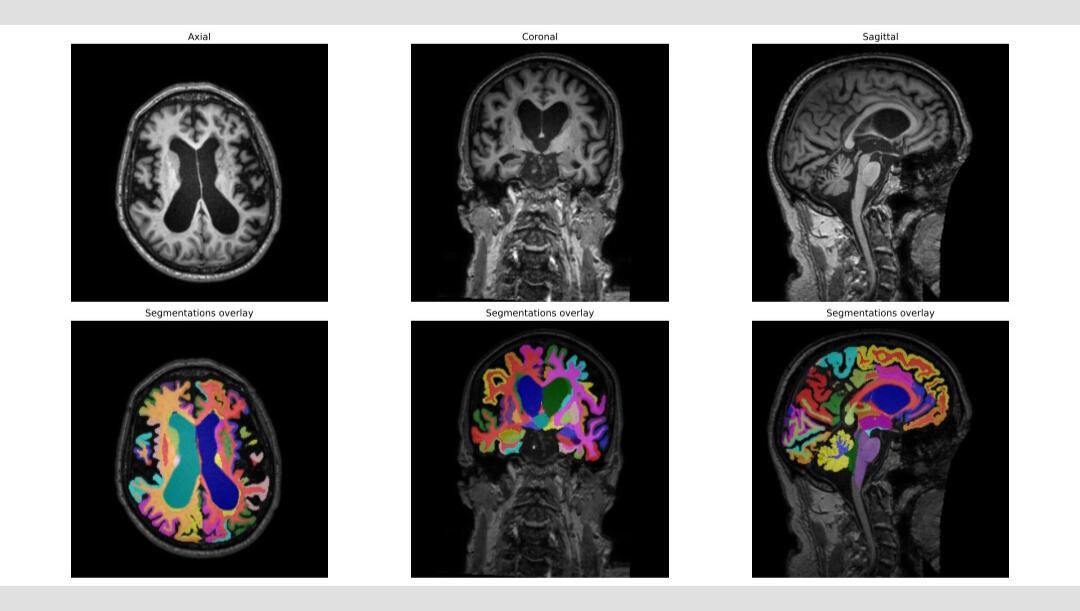

Quantitative Brain Analysis - Dementia Diagnostics

Delta Age

Δ(age) = radiological brain age – biological age"Brain age" is the apparent age of an individual, as inferred from brain imaging data. The difference between brain age and actual age (the "delta") may reflect accelerated aging (positive delta) or resilience (negative delta). It has been found to be a useful correlate with factors such as disease and cognitive decline, in other words to be an independent biomarker of brain disease.